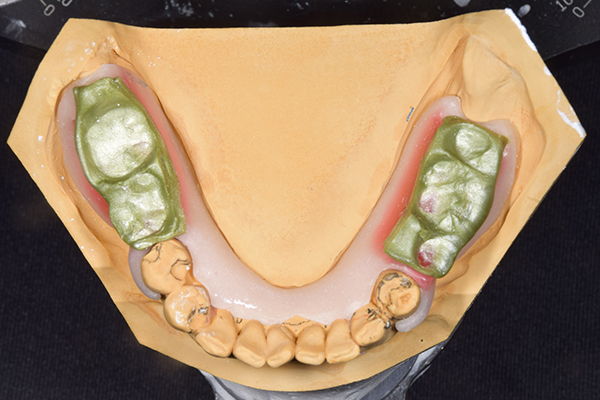

下の入れ歯

そこで、安定をよくするために、右の奥歯の位置にインプラントをいれて、義歯が揺れない様にすることにしました。

治療内容 レントゲンをみて最低限の長さのインプラントを右上の奥歯の位置に埋入しました。インプラントと骨の結合(オッセオインテグレーション)と歯肉の治癒を待ち、アバットメントをいれて型取りをして、入れ歯を作成しました。極力薄くするために、金属をもちいた入れ歯にしました。